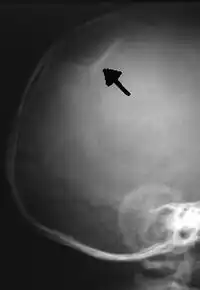

The material factual allegations of the amended complaint are as follows. Plaintiff was born on May 14, 1970. On repeated occasions during the first year of her life she was severely beaten by her mother and the latter's common law husband, one Reyes. On April 26, 1971, when the plaintiff was eleven months old, her mother took her to the San Jose Hospital for examination, diagnosis, and treatment. The attending physician was defendant Dr. Flood, acting on his own behalf and as agent of the defendant San Jose Hospital. At the time, the plaintiff was suffering from a comminuted spiral fracture of the right tibia and fibula, which gave the appearance of having been caused by a twisting force. Plaintiff's mother had no explanation for this injury. Plaintiff had bruises over her entire body. In addition, she had a non-depressed linear skull fracture which was then in the process of healing. Plaintiff demonstrated fear and apprehension when approached. Inasmuch as all plaintiff's injuries gave the appearance of having been intentionally inflicted by other persons, she exhibited the medical condition known as the battered child syndrome.

It is alleged that proper diagnosis of plaintiff's condition would have included taking X-rays of her entire skeletal structure, and that such procedure would have revealed the fracture of her skull. Defendants negligently failed to take such X-rays, and thereby negligently failed to diagnose her true condition. It is further alleged that proper medical treatment of plaintiff's battered child syndrome would have included reporting her injuries to local law enforcement authorities or juvenile probation department. Such a report would have resulted in an investigation by the concerned agencies, followed by a placement of plaintiff in protective custody until her safety was assured. Defendants negligently failed to make such report.

For example, the leading article by Kempe et al., op. cit., supra,[10] states that "A physician needs to have a high initial level of suspicion of the diagnosis of the battered-child syndrome in instances of subdural hematoma, multiple unexplained fractures at different stages of healing, failure to thrive, when soft tissue swelling or skin bruising are present, or in any other situation where the degree and type of injury is at variance with the history given regarding its occurrence . . . ." (Id., at p. 20.) Of the different types of fractures exhibited, an arm or leg fracture caused by a twisting force is particularly significant because "The extremities are the 'handles' for rough handling" of the child by adults. (Id., at p. 22.) The article also contains numerous recommendations to conduct a "radiologic examination of the entire skeleton" for the purpose of confirming the diagnosis, explaining that "To the informed physician, the bones tell a story the child is too young or too frightened to tell." (Id., at p. 18.) Finally, on the subject of management of the case it is repeatedly emphasized that the physician "should report possible willful trauma to the police department or any special children's protective service that operates in his community" (id., at p. 23) in order to forestall further injury to the child: "All too often, despite the apparent cooperativeness of the parents and their apparent desire to have the child with them, the child returns to his home only to be assaulted again and suffer permanent brain damage or death." (Id., at p. 24.)